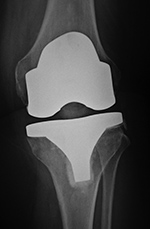

| Posterior cruciate retaining total knee arthroplasty (TKA) |

| Posterior cruciate retaining total knee prosthesis with cementless femoral and cemented tibial component and patellar resurfacing |